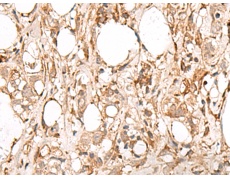

IHC positive control: |

Human esophagus cancer and Human breast cancer |

IHC Recommend dilution: |

50-300 |